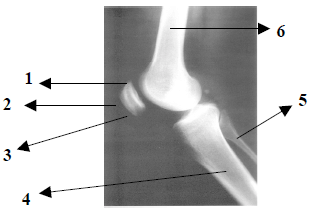

Observe atentamente a imagem radiográfica abaixo e responda:

Pela anatomia radiológica demonstrada na imagem, podemos afirmar que trata-se da incidência

perfil de joelho.